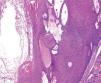

El estudio histopatológico mostró una lesión crateriforme, bien delimitada, con el centro ocupado por material queratósico que comunicaba con la superficie externa de la piel y la base constituida por un epitelio escamoso hiperplásico donde se evidenciaba queratinización tricolémica (fig. 2). El epitelio estaba constituido por una primera capa periférica de células cuboideas, dispuestas en empalizada, que se asentaban sobre una membrana basal y varias capas suprayacentes constituidas por células escamosas grandes, de citoplasma amplio y pálido (fig. 3), que queratinizaban de forma abrupta, sin mediar capa granulosa previa y dando lugar a una queratina eosinófila, compacta y ortoqueratósica (fig. 4). En la base del tumor se podían observar pequeñas estructuras que recordaban a quistes tricolémicos en miniatura. Se estableció el diagnóstico de cuerno tricolémico o queratosis tricolemal.